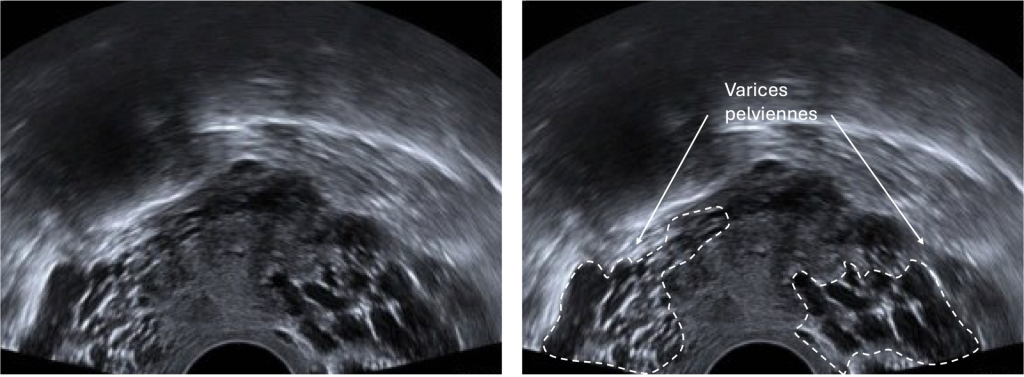

Quels examens permettent de diagnostiquer des varices pelviennes ?

Différents examens permettent de faire le diagnostic de varices pelviennes et d’exclure d’autres pathologies comme les fibromes ou l’adénomyose

Échographie Doppler pelvienne : premier examen, non invasif, permettant de visualiser les veines dilatées et le reflux sanguin.